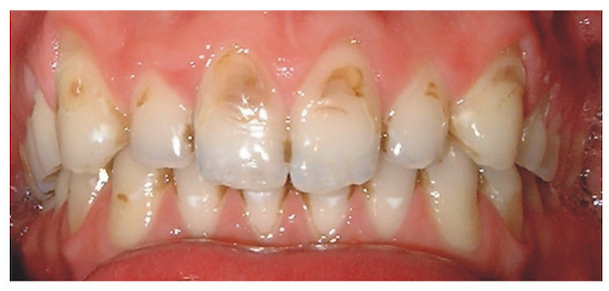

Initially the teeth may looks shiny or have translucent edges, but eventually you start developing pits and cavities as above.

Most composite repairs will begin to stain or wear away, especially if one continues drinking fizzy drinks. In the case above the gentleman was 26 years old and had for many years been replacing the anterior fillings.

He wanted a better solution and we firstly asked him to drink still water and refrain from all fizzy drinks. A diet analysis was also carried out to see if he was eating anything too sweet etc.